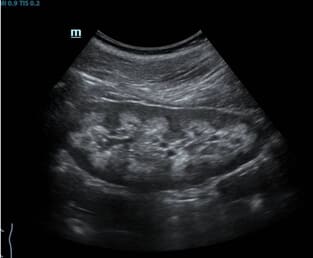

- Разбира се. Първият случай е свързан с камъни в бъбреците. С мен се свърза 27-годишен мъж с болка в дясната страна която започва от гърдите и завършва някъде в областта на пикочния мехур. Болката се проявяваше с кратки спазми, конвулсии, студена пот и се появяваше на вълни. Изображението показва наличието на 19 мм камък, заседнал в горната част на бъбрека. Предписахме Nefro Aktiv . за разбиване на камъни в бъбреците. В рамките на два дни от използването му камъкът започна да се чупи и излезе напълно за една седмица. Пациентът не чувства дискомфорт.

Вторият случай е свързан с киста с диаметър 3 cm. Болестта обикновено преминава без симптоми. Не боли, резултатите са добри, уринирането протича гладко. Ето защо кистата беше толкова голяма. 22-годишното момиче се страхуваше от операция. Изписахме й Nefro Aktiv . В рамките на месец повторният преглед не показа никаква патология.